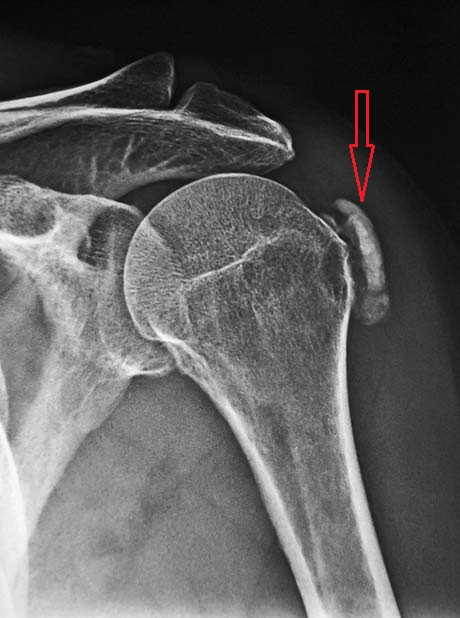

Ασβεστοποιός Τενοντίτιδα

Με τον όρο «ασβεστοποιός τενοντίτιδα» εννοούμε την πάθηση κατά την οποία έχουμε εναπόθεση αλάτων ασβεστίου, συνήθως υδροξυαπατίτη, σε περιαρθρικούς ιστούς και κυρίως στους τένοντες κοντά στα σημεία που προσκολλώνται πάνω στα οστά. Η εναπόθεση αλάτων ασβεστίου μπορεί να είναι διάχυτη ή να συσσωρεύεται σε ένα σημείο, οπότε είναι ακτινολογικά ορατή. Η εμφάνιση της νόσου είναι πιό συχνή στους ενήλικες μεταξύ 30 και 50 ετών και είναι λίγο πιό συχνή στις γυναίκες.

Η αιτιολογία της ασβεστοποιού τενοντίτιδας δεν είναι πλήρως γνωστη.Οι περιαρθρικές εναποθέσεις αλάτων ασβεστίου μπορεί να είναι ασυμπτωματικές.Σε ορισμένες περιπτώσεις όμως κρύσταλλοι ασβεστίου αποσπώνται από τις εναποθέσεις, εισέρχονται σε παρακείμενο ορογόνο θύλακο και προκαλούν έντονη τοπική φλεγμονή που εκδηλώνεται με πολύ ισχυρό πόνο, διόγκωση, θερμότητα και έντονη τοπική ευαισθησία στην πίεση.